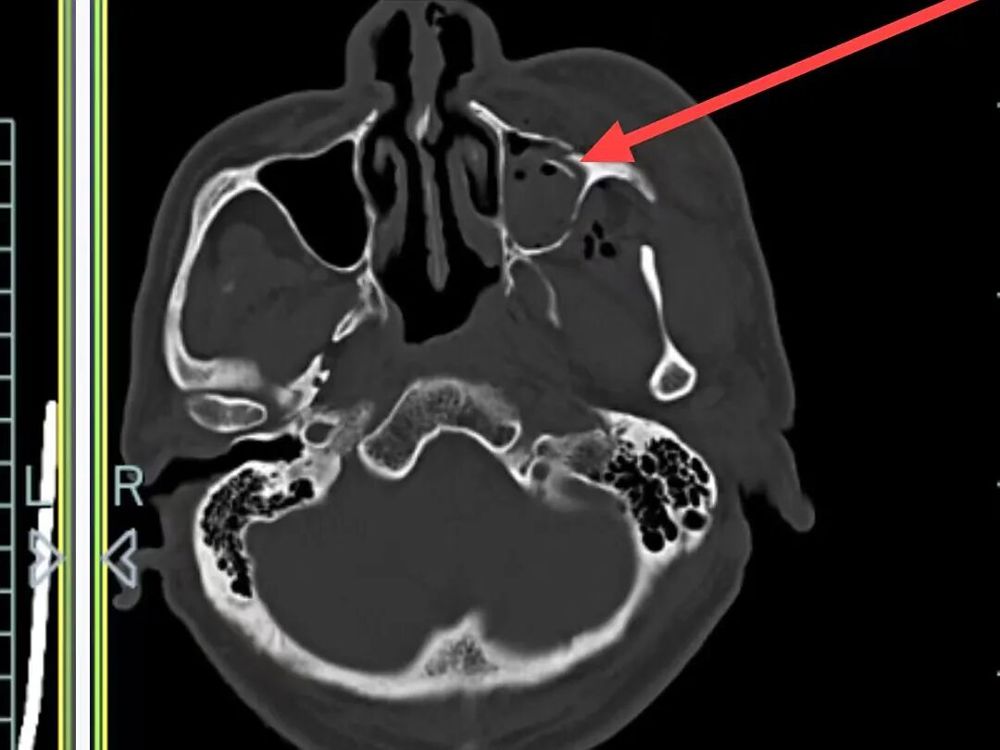

外侧壁、左眼眶外侧壁骨折、左侧颌面部软组织肿胀,软组织内积气

左侧颞骨、左侧颧弓、左侧上颌窦前壁骨折